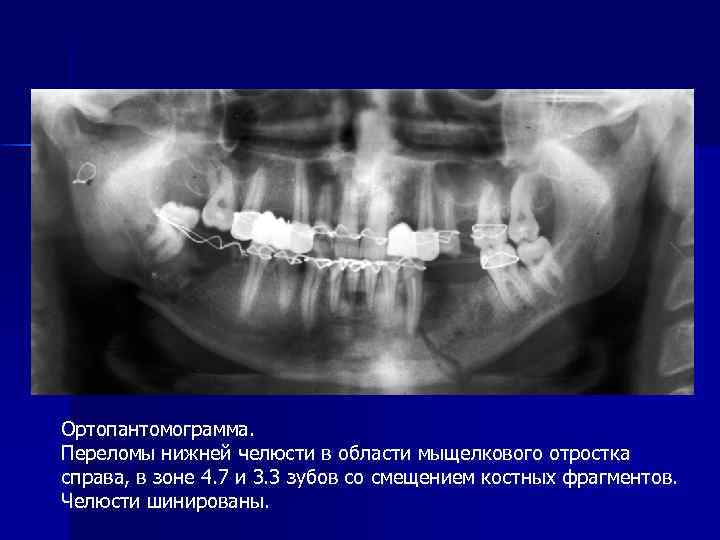

Ортопантомограмма. Переломы нижней челюсти в области мыщелкового отростка справа, в зоне 4. 7 и 3. 3 зубов со смещением костных фрагментов. Челюсти шинированы.